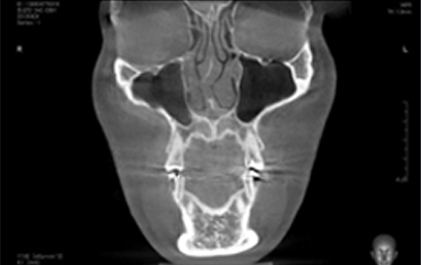

3D-CT

입체분석을 통한

심층검사

수술 전 3D-CT 입체 분석을 통해

환자의 코 뼈는 물론 코 주변 연부 조직의

모양, 상태, 크기까지 정밀하게 검사하여

환자 개개인에 맞는 1:1 맞춤 수술을 계획합니다.

연골 비대칭 및

비중격 만곡증의 유무

하비갑개 비후 및

코막힘 문제해결

비중격 연골의

상태와 크기 분석

코 뼈의 넓이